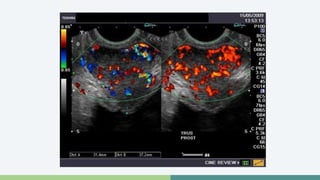

Ultrasonografía

• TRUS se realiza después de un DRE anormal o PSA elevado

• Biopsias

• Lesiones hipoecoicas (60-70%)

• Lesiones hiperecoicas (30-40%)

Ultrasonografía • TRUSse realiza después de un DRE anormal o PSA elevado • Biopsias • Lesiones hipoecoicas (60-70%) • Lesiones hiperecoicas (30-40%)